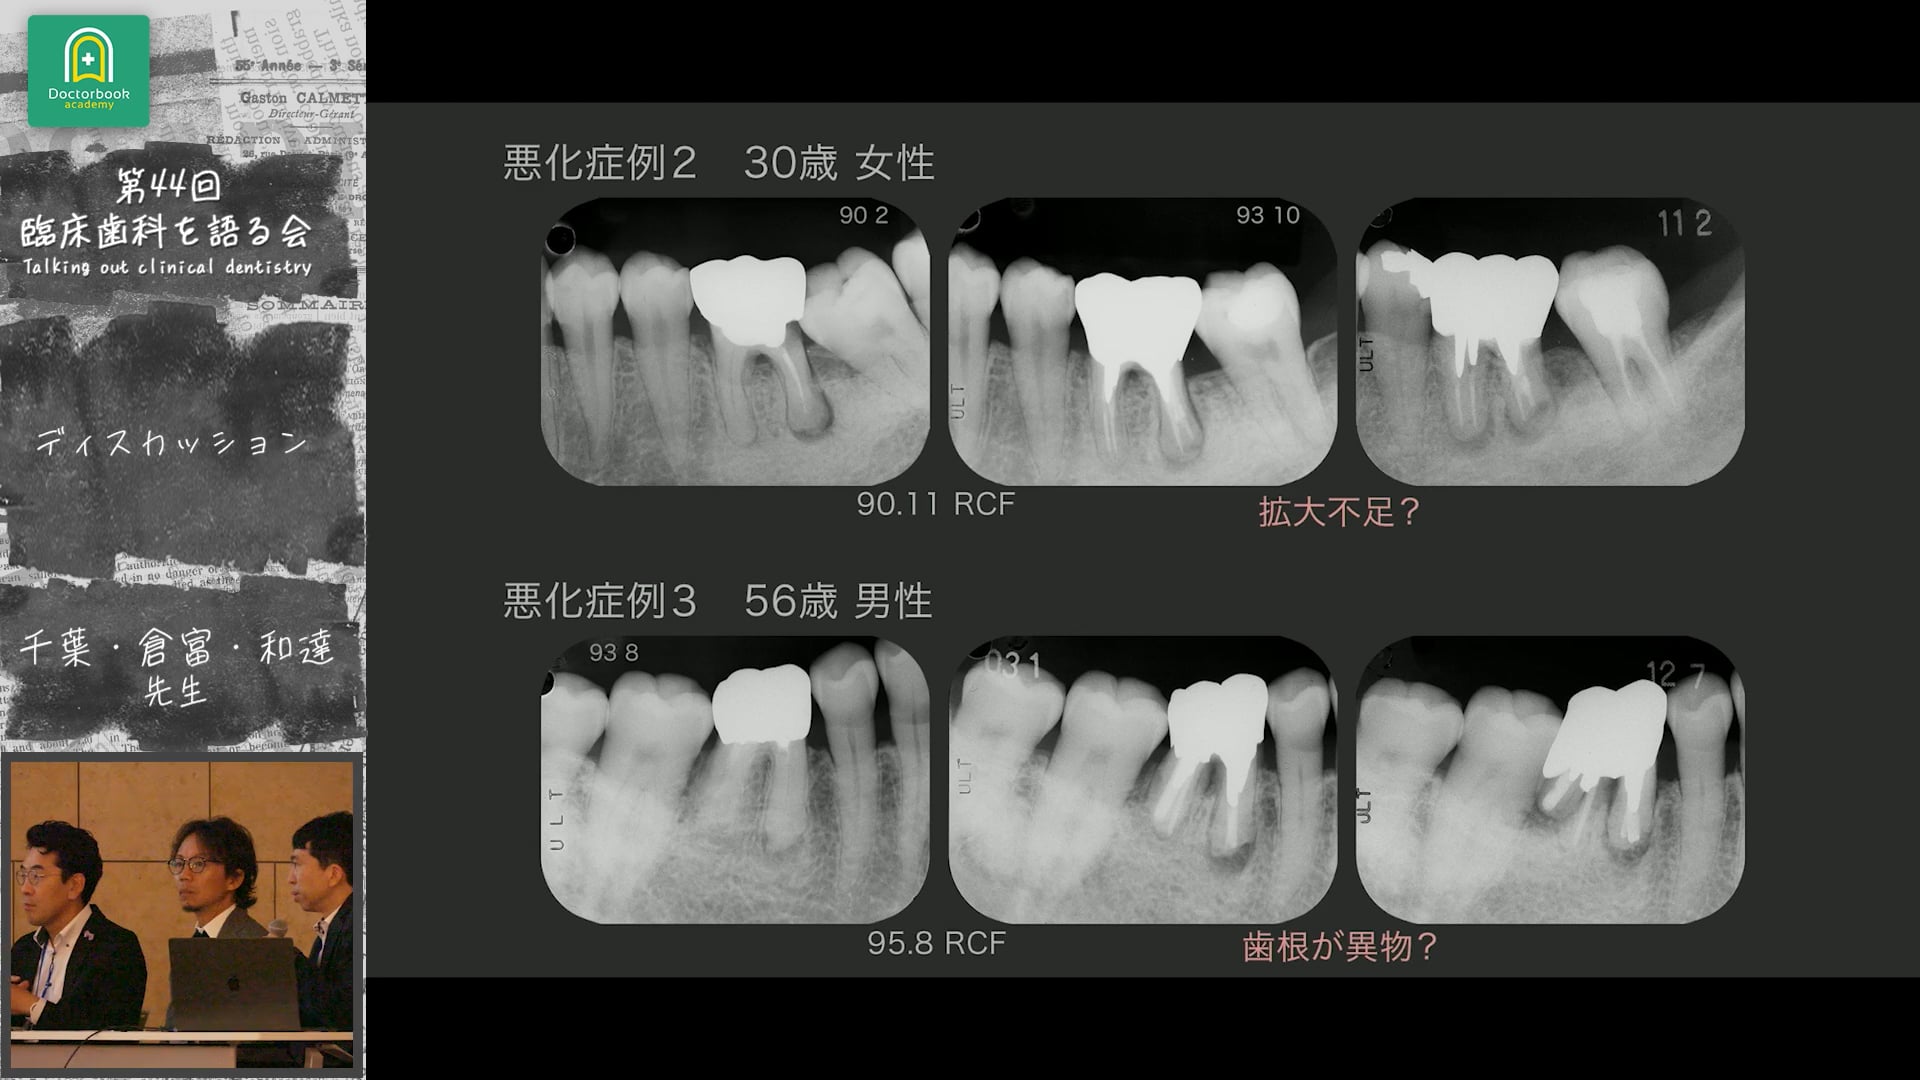

和達先生・倉富先生・千葉先生を中心に、根管治療における診断・治療限界・歯の保存と抜歯判断、そして水酸化カルシウム製剤の使い分けについて活発な意見交換が行われました。

「根管治療は歯科医の良心」という言葉を軸に、再根管治療の意義や、保存と再治療のバランスをどう取るかについても議論。